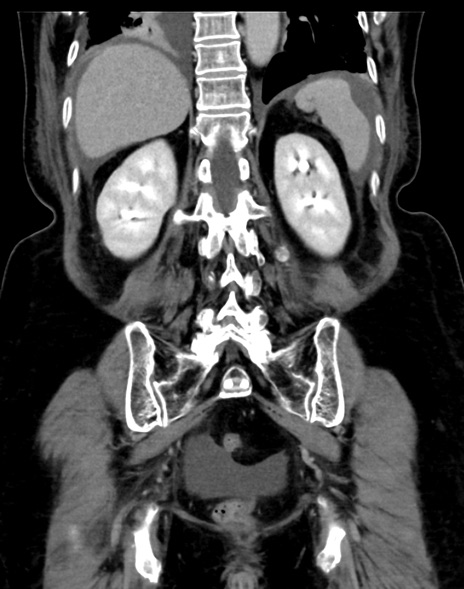

症例13 CT(冠状断像)1日半後